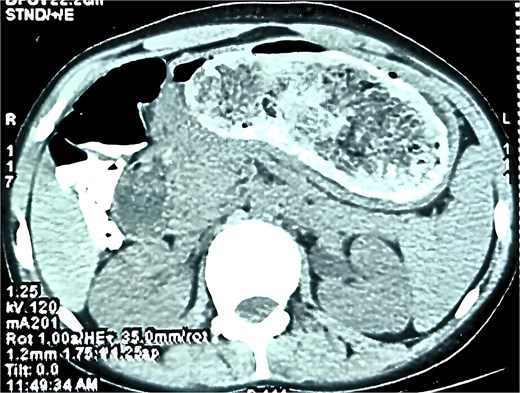

A contrast-enhanced CT scan of the abdomen (Fig. 1) showed a large, clearly outlined intraluminal mass measuring 50.6 × 114.6 × 82.1 mm, stretching from the stomach into the duodenum and jejunum. The mass had a mottled gas pattern, a feature typical of bezoars. The jejunum demonstrated a transient intussusception with proximal bowel dilatation and the classic ‘target sign’, supporting the diagnosis of Rapunzel syndrome with jejunojejunal intussusception.

Computed tomography (CT) is the best modality for diagnosis. CT typically shows a non-enhancing intraluminal mass with a mottled gas pattern due to trapped air within the hairball [2, 6]. It also demonstrates the extent of the bezoar, including the tail and associated complications such as obstruction or intussusception. In this case, CT showed both the trichobezoar and transient jejunojejunal intussusception, aiding surgical planning. The ‘target sign’ confirmed the intussusception, and proximal bowel dilatation indicated obstruction.